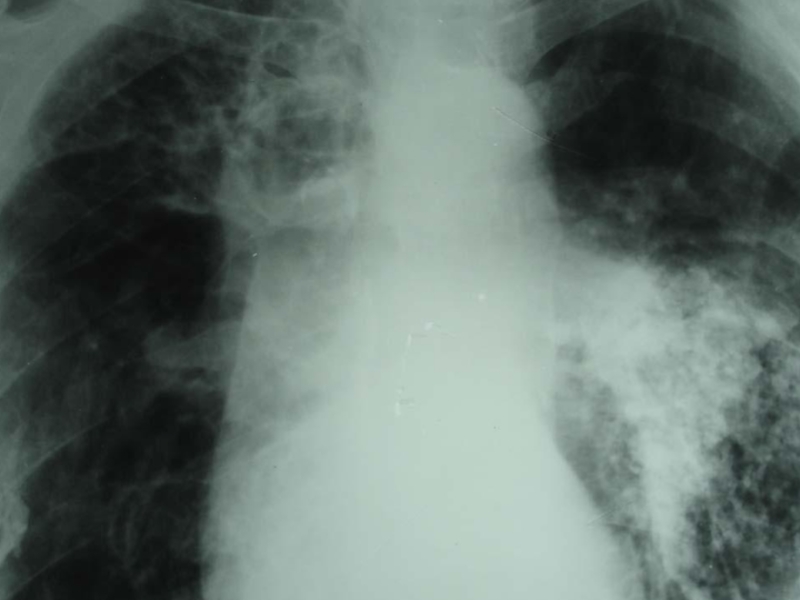

Слайд 28Хронический диссеминированный туберкулез

При хроническом диссеминированном туберкулезе преобладает продуктивная тканевая

реакция. При этом уплотненные и более крупные очаги располагаются в

верхних отделах легких, меньшей величины – в нижних. Наряду с очагами в наружно задних отделах верхних долей имеются рубцы.

Могут быть штампованные каверны, петрификаты.

Характерен диффузный сетчатый склероз, эмфизема.

Обычно формируется хроническое легочное сердце.